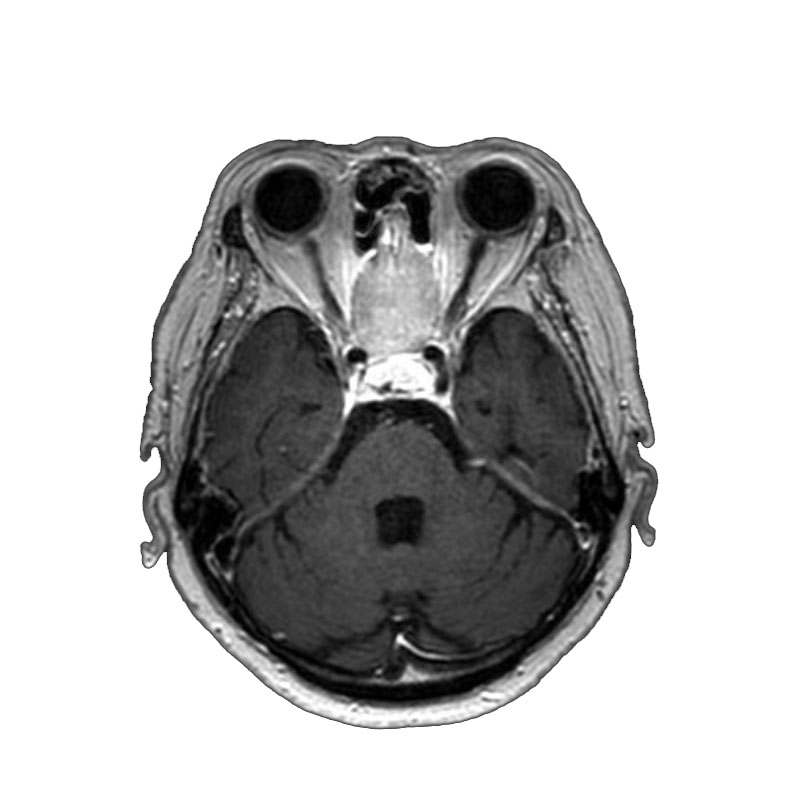

5月12日(火)

脳動脈瘤(Rt.IC-PC)

フローダイバーター留置術

芝野/古谷/木本

脳動脈瘤(Lt.IC-PC)